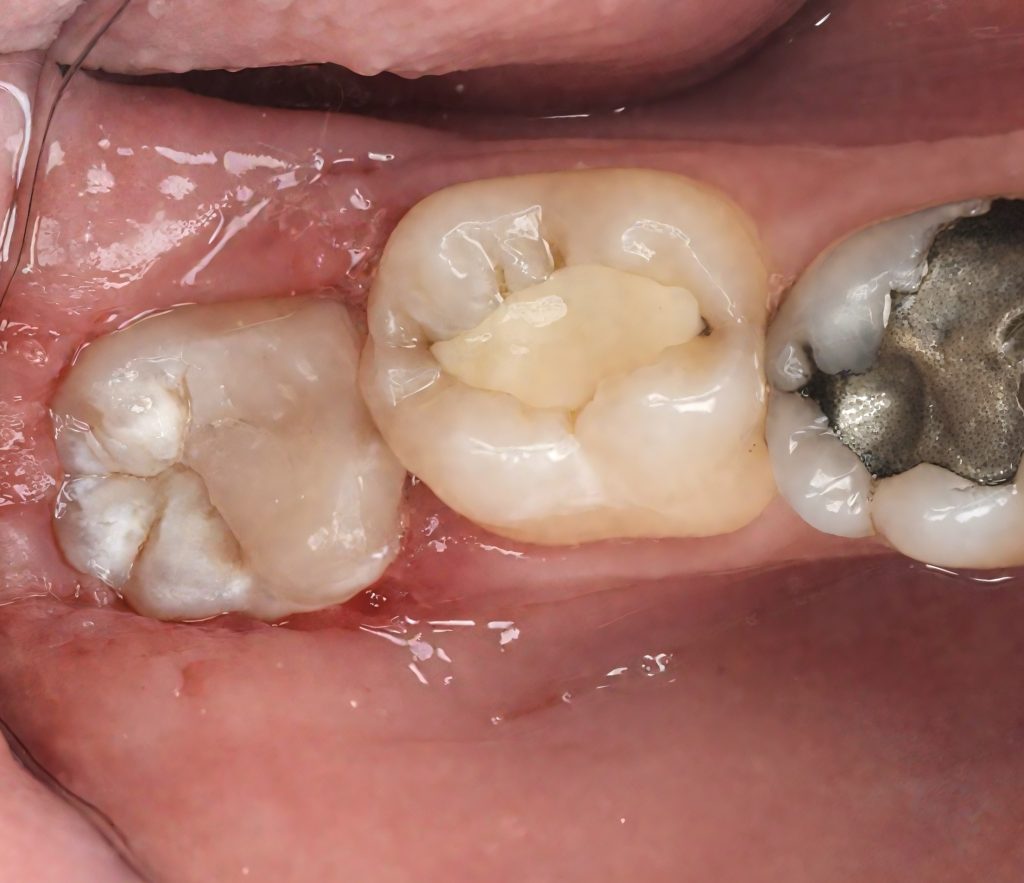

Due to limited access and infra-occlusion, rubber-dam isolation was achieved using a modified split-dam technique with floss ligatures and PTFE retraction (Fig 2). Microscope magnification allowed moisture control and precise visibility during adhesive procedures.

- Fig 2: Split-dam isolation under microscope.